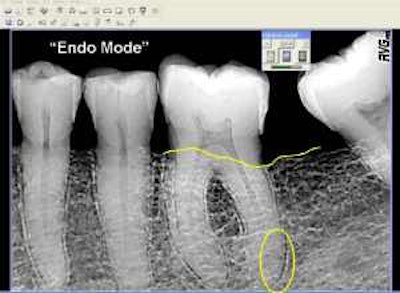

- Greater accuracy. "Most errors are darkroom errors," says Allan Farman, B.D.S., M.B.A., Ph.D., D.Sc., of the University of Louisville. Digital x-rays preserve much more information than the human eye can perceive, and image management software can highlight details you might otherwise miss. In one study, Dr. Farman found that observers using solid-state digital x-rays were successful 55 percent of the time in detecting the second mesiobuccal canal in maxillary molars, compared to 44 percent for those using film. (Observers using storage phosphor were only successful 39 percent of the time.)

| This is the same x-ray in "endo" mode. (Screen shots courtesy of Allan G. Farman). |